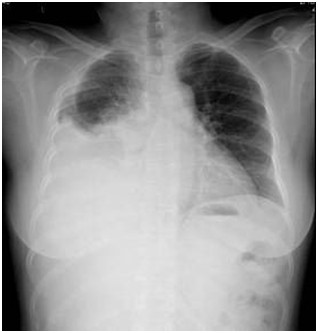

05卷-3.老年女性,60歲,咳嗽、咳痰伴氣促3小時(shí)入院,胸片提示(本題滿分2.00分)

A.氣胸

B.間質(zhì)性肺炎

C.病毒性肺炎

D.胸腔積液

本題答案:D

【該題針對(duì)“ X線-胸腔積液 ”知識(shí)點(diǎn)進(jìn)行考核】